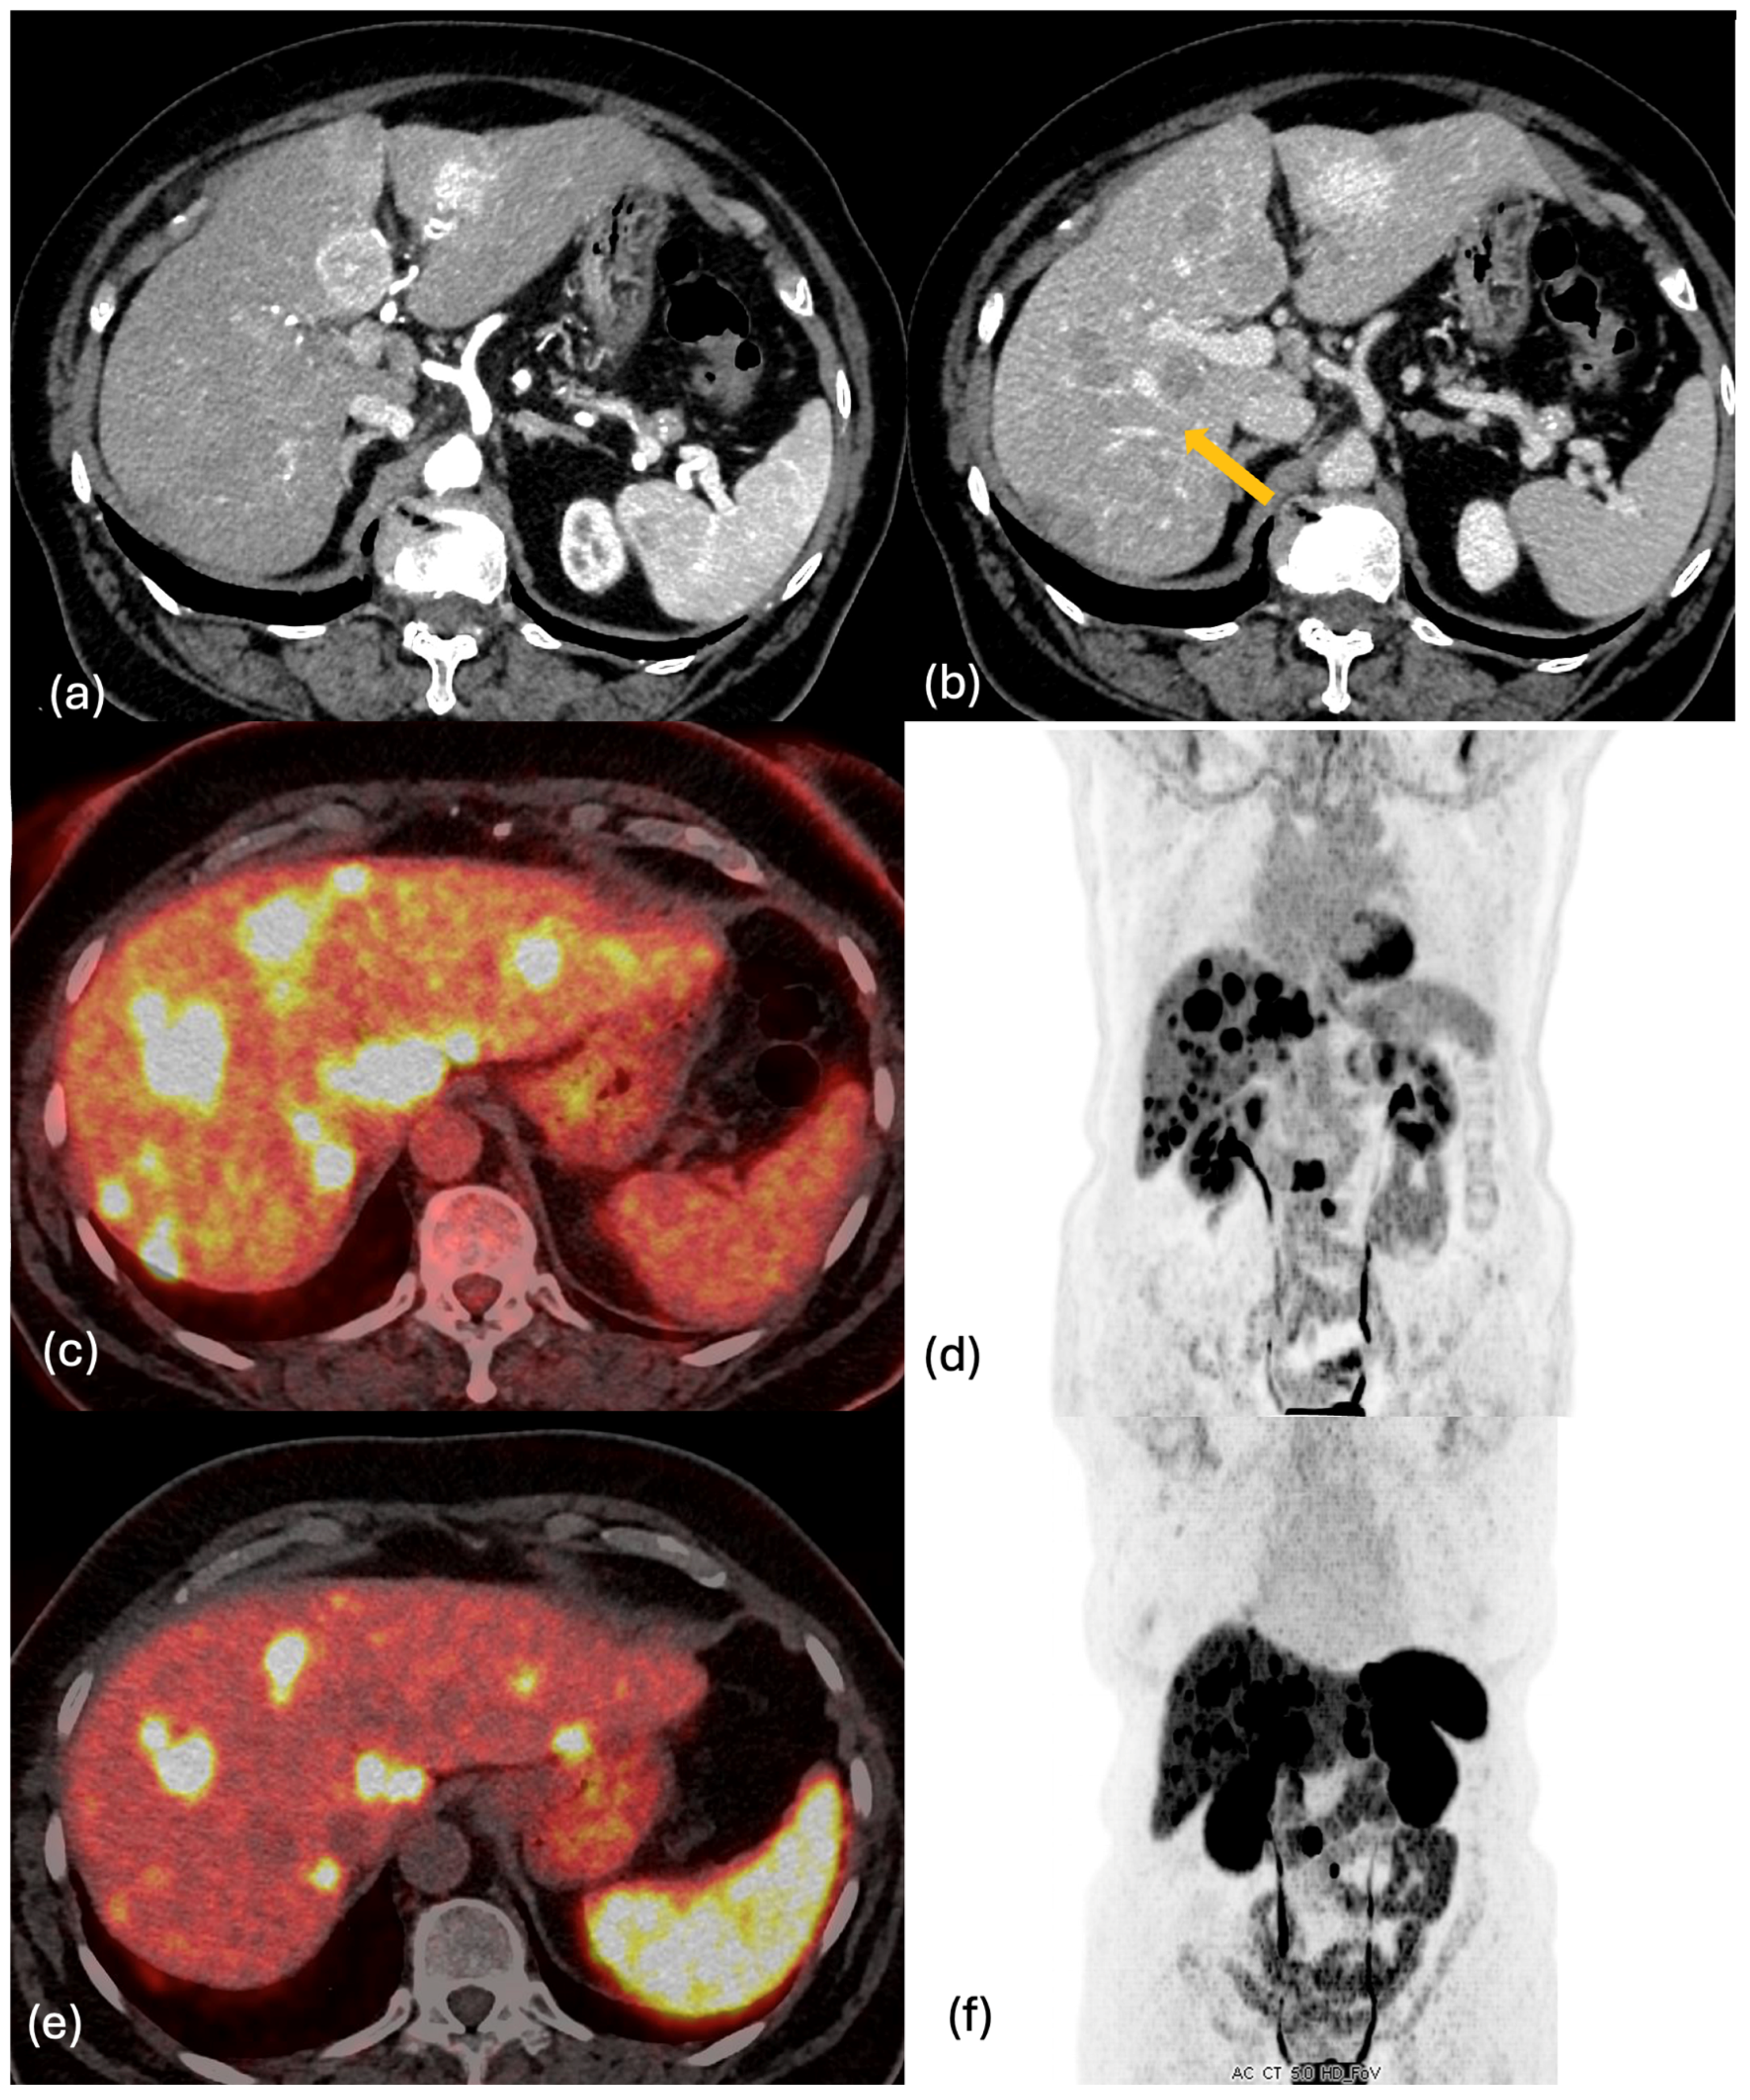

2.2. CT

2.4. PET-CT